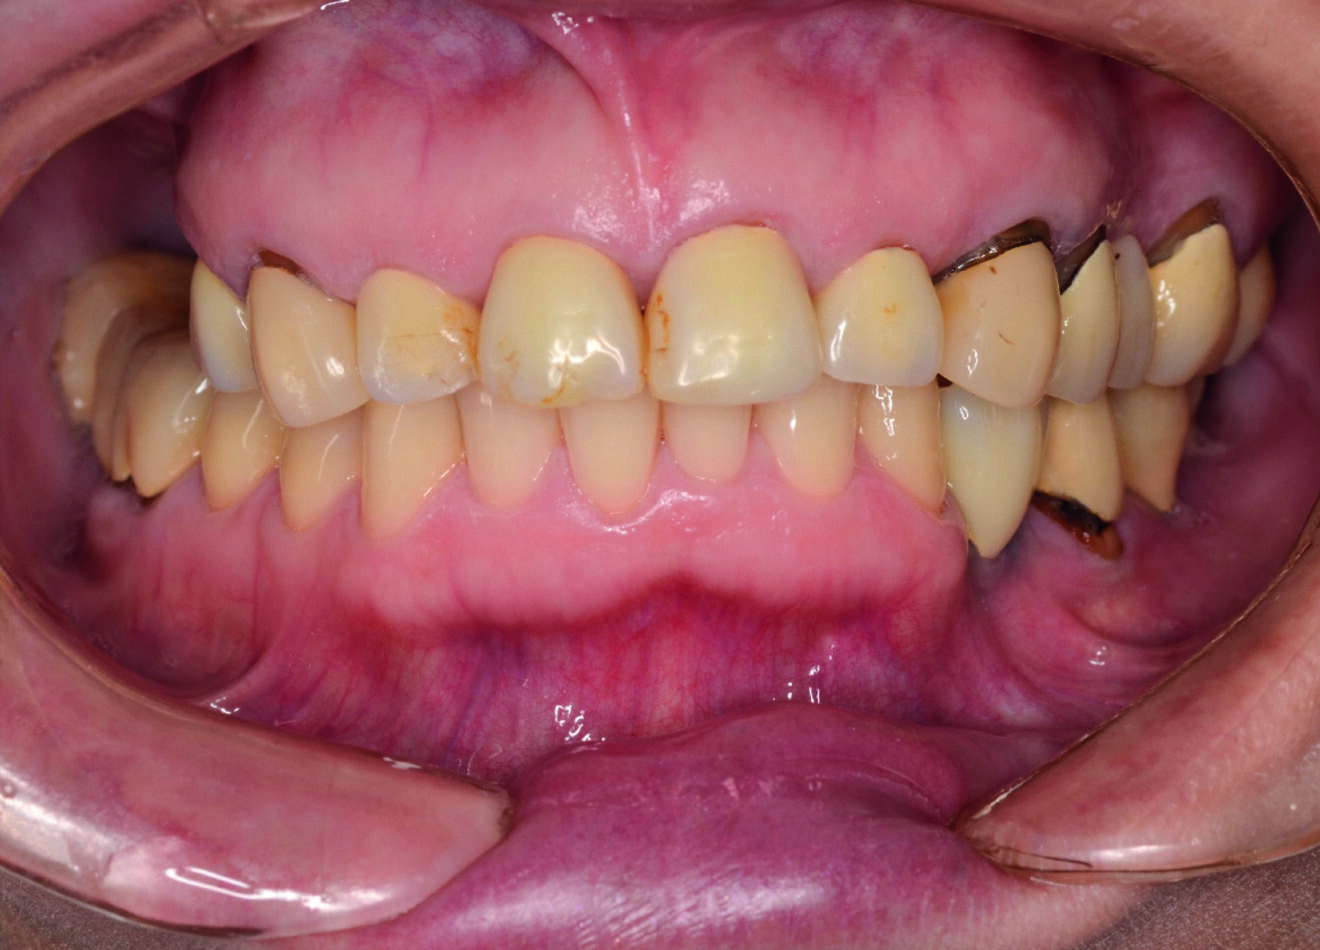

Une patiente de 50 ans atteinte d’une péri-implantite à un stade avancé, s’est présentée à notre laboratoire avec le souhait d’une restauration fonctionnelle et esthétique (Figs. 2a et b). Nous avons établi un plan de traitement qui consistait à traiter la péri-implantite, à poser de nouveaux implants et, finalement, à améliorer l’esthétique générale. Notre première étape a été de reconstruire complètement l’occlusion par une restauration en zircone Zolid FX Multilayer (Amann Girrbach), sauf pour les dents antérieures inférieures.

Fig. 2a : Situation initiale avec péri-implantite à un stade avancé.

Fig. 2 b : Situation initiale avec péri-implantite à un stade avancé.